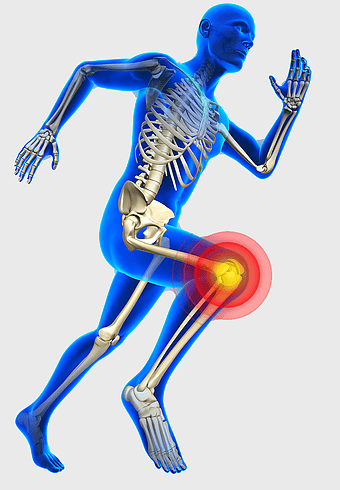

771x1111px

knee pain sports injury, physical therapy for athletes, human knee bones anatomy, joint focus in running, skeletal health in sports, musculoskeletal injury prevention, running biomechanics analysis -